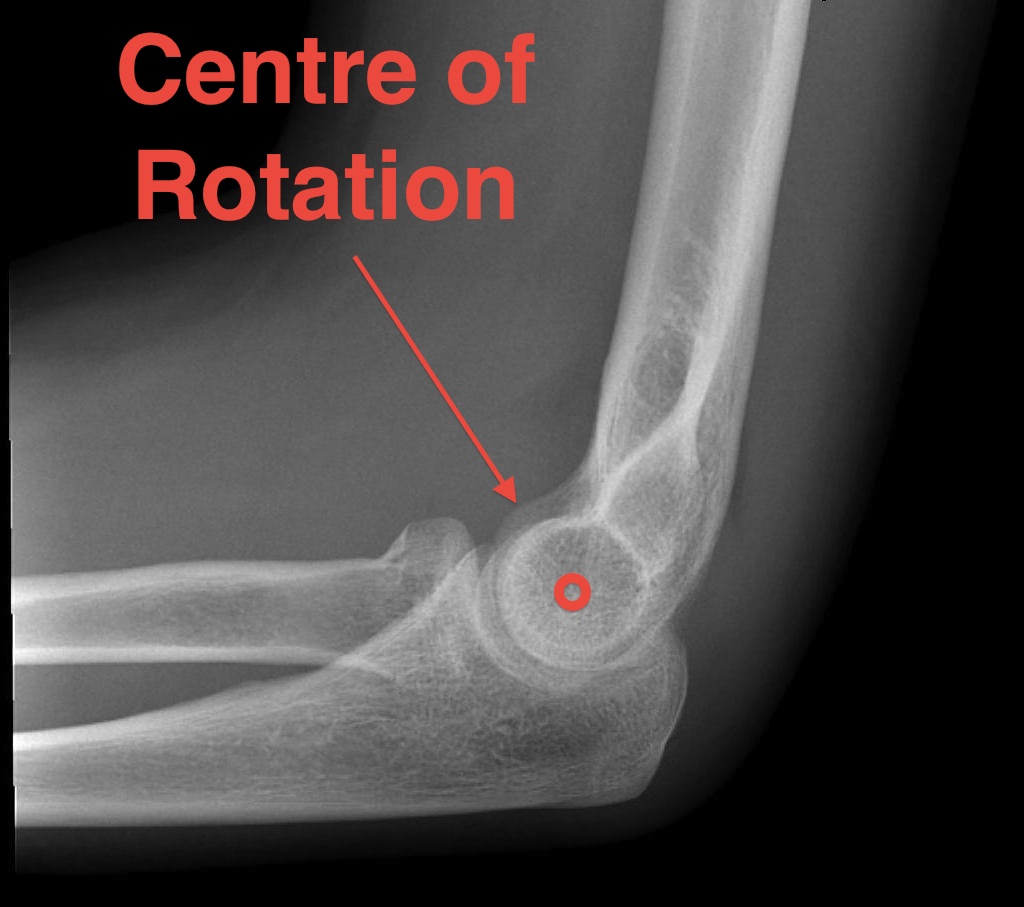

Centre of rotation - trochlea - centre of rotation anterior to humeral shaft |

- centre of rotation is center of capitellum